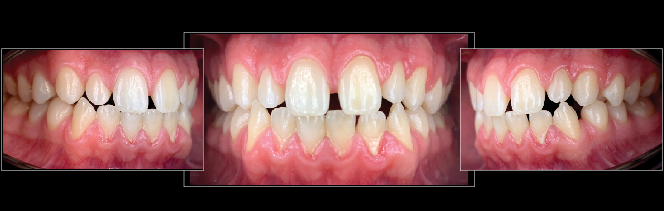

Fig 11. Esthetic treatment planning for a patient presenting for veneers is aided by the use of the SDL for photos taken by a dental assistant.

Figure 11